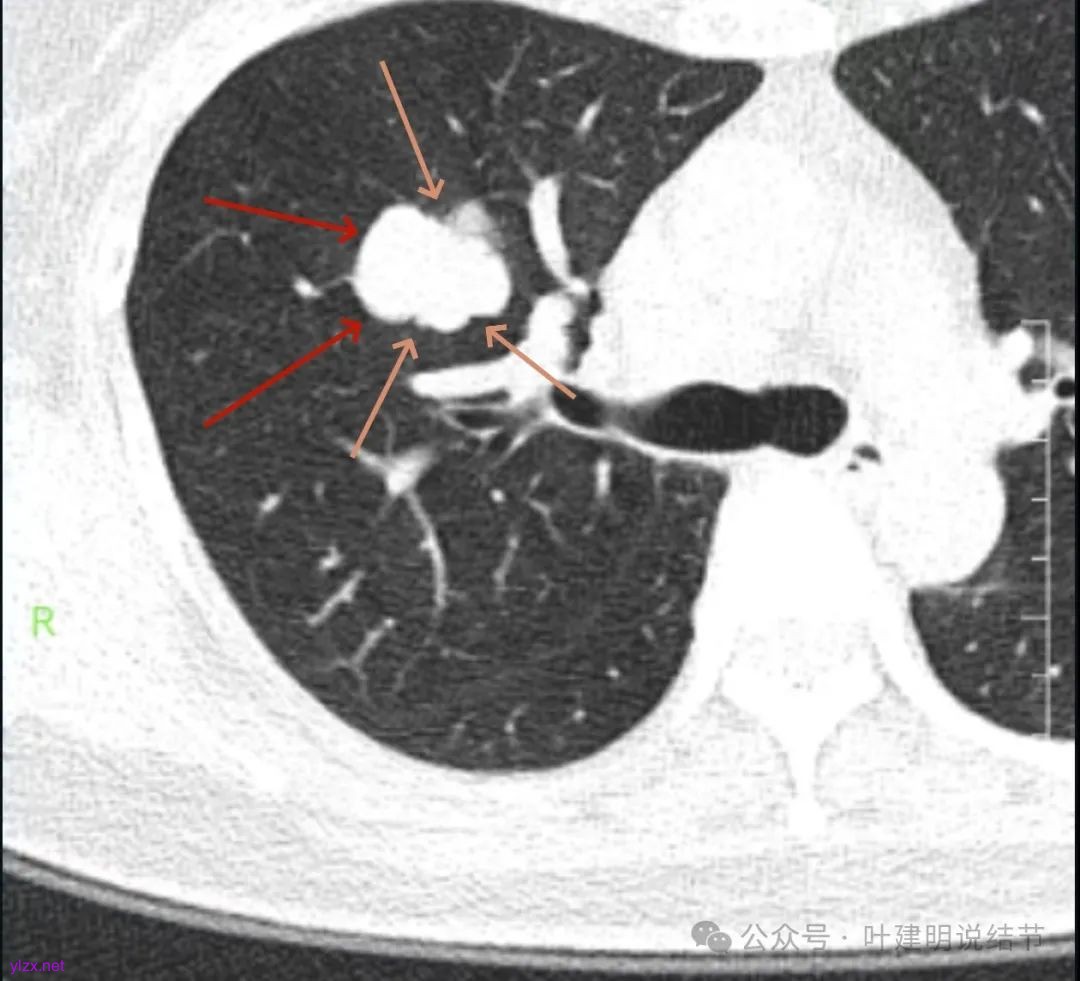

影像展示与分析:

腔静脉旁明显肿大淋巴结。

你的右上叶这个病灶基本上肯定是肺癌,要尽快处理。从影像上看有以下特点:1、整体轮廓清楚,不似普通炎症的周围有晕或阻塞性改变;2、边缘明显的浅分叶,总体上的感觉膨胀性明显,不管哪个层面看上去都是鼓鼓的;3、边缘区域有磨玻璃成分而且也是分叶状的;4、部分层面见血管进入;5、空腔病灶的壁厚薄不均,内壁不光滑。我考虑中低分化肺癌,由于腔静脉旁有明显肿大淋巴结,需要进一步完善增强CT以及PET-CT检查以明确有无远处转移,是否仍可手术治疗(从病灶本身来说是可以肺叶切除治疗的)。要尽快处理。意见供参考!